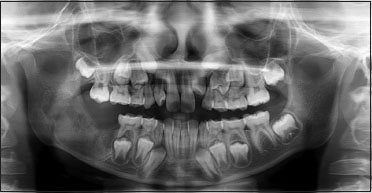

Based on the history and clinical examination, a provisional diagnosis of ameloblastoma was made. Under differential diagnosis, ameloblastic fibroma and odontogenic keratocyst were considered. Intaoral periapical view (IOPA), occlusal view,orthopantomogram (OPG), and computed tomography (CT) scan were taken. IOPA taken in relation to 85 and 46 [Figure 1] showed diffuse radiolucency distal to 46 with the absence of 47 tooth bud. OPG [Figure 2] view showed a solitary, well-defined radiolucency of size 3 cm × 2 cm extending anteroposteriorly from mesial root of the tooth number 46 is 1 cm from the posterior border of the ramus of the mandible, superoinferiorly 1 cm below the sigmoid notch, to the inferior border of the mandible thinning the inferior cortical margin. Internal structure was radiolucent with the displaced tooth bud of 47 in the ramus region.

| Figure 1:Intraoral periapical radiograph showing diffuse radiolucency distal to 46 with the absence of 47 tooth bud

| Figure.2:Preoperative orthopantomogram showing solitary, well‑defined radiolucency of size 3 cm × 2 cm surrounding the crown of 47 tooth bud which got displaced into the ramus region with thinning of the inferior border of the mandible